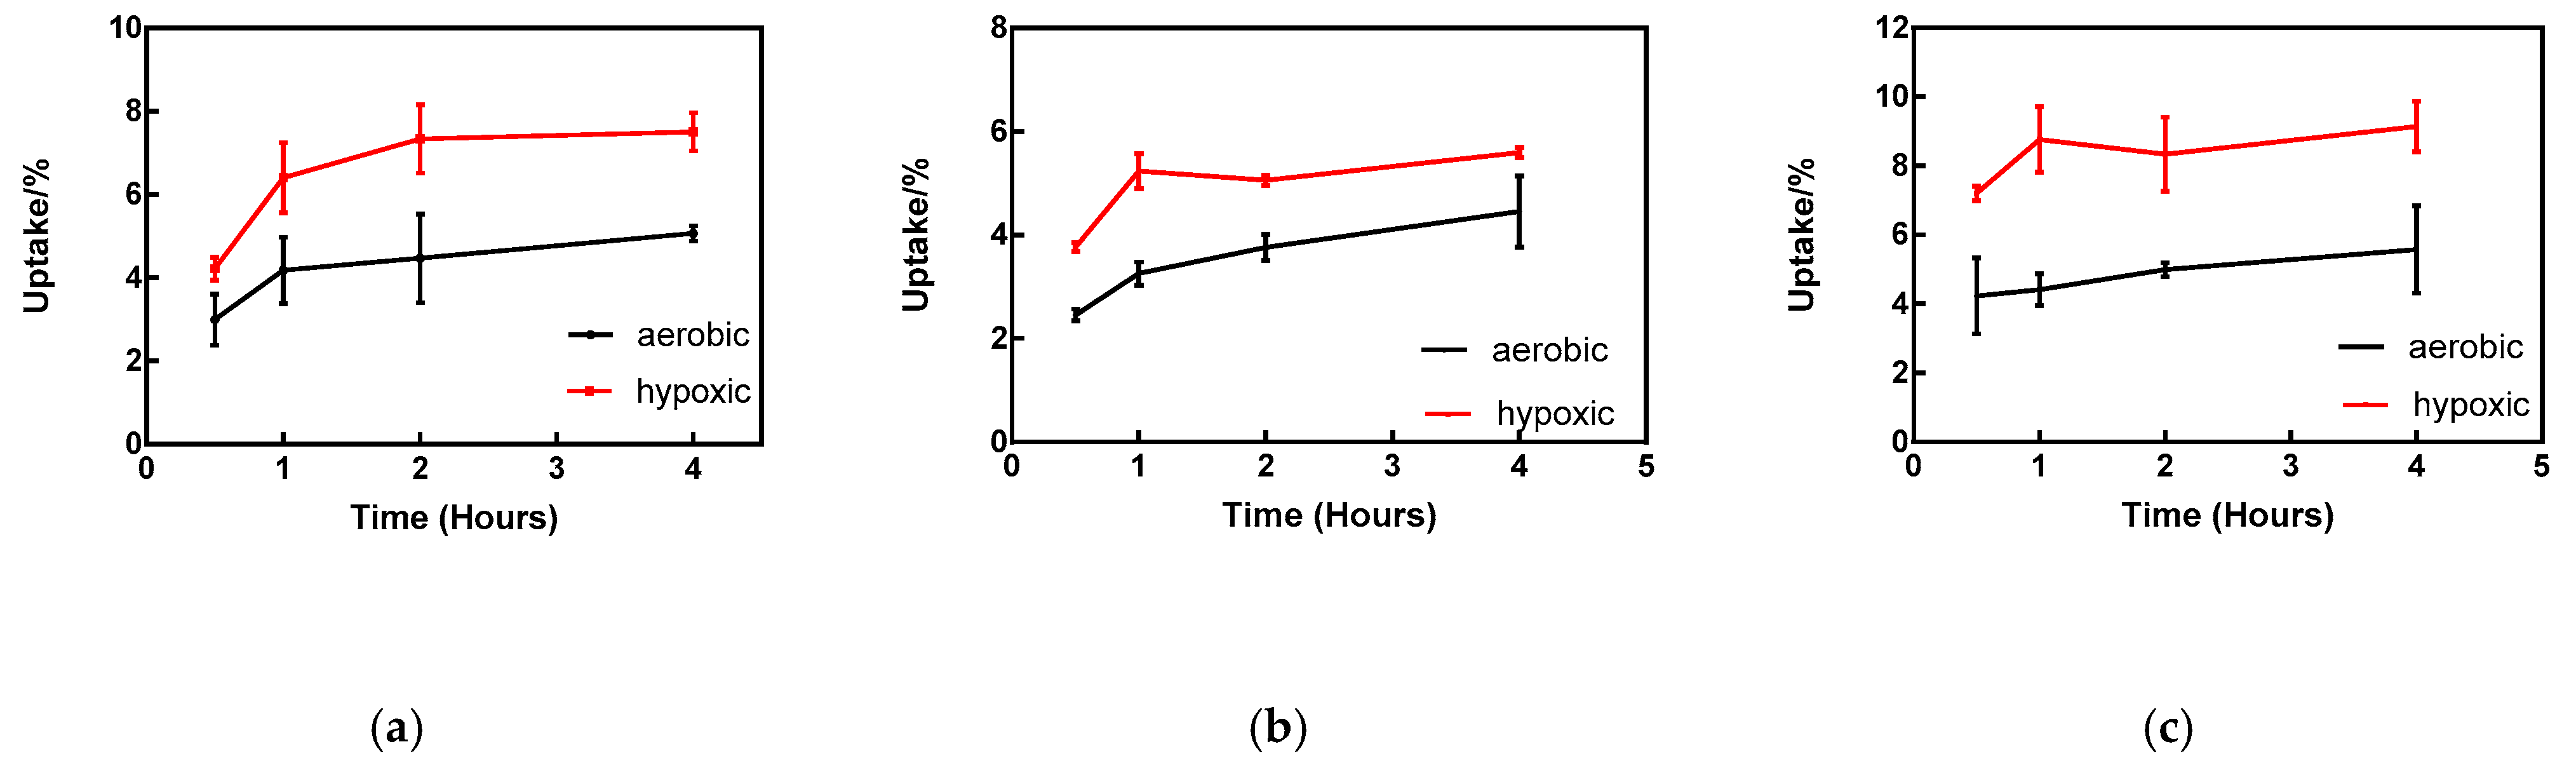

2.4. In Vitro Cellular Uptake

4.6. In Vitro Cellular Uptake